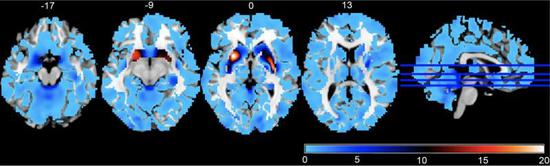

上图是精神分裂症的一个风险基因位点与全脑灰质体积关联性的3维空间分布;红色越深表示统计显著性越高,其次是黄色、绿色,统计显著性最低是蓝色。右图是最显著的脑区(壳核)灰质体积与全基因组变异位点关联性的曼哈顿图。结果按照染色体序号排列。